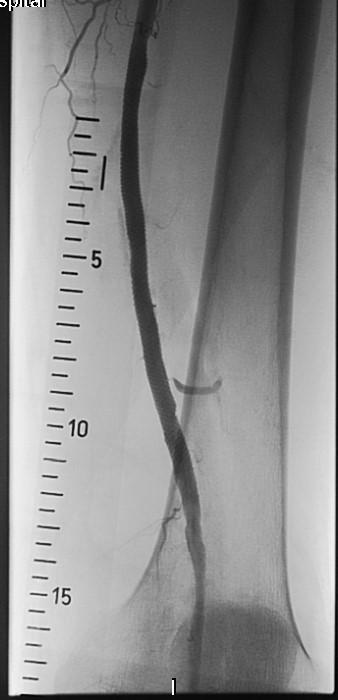

Они провели пациенту высокотехнологичную малоинвазивную операцию по восстановлению проходимости артерии − баллонную ангиопластику и стентирование. После операции просвет артерии восстановился – пациенту удалось сохранить ногу. Более того, ходить он может теперь долго и без боли, а значит, человеку вернули активную полноценную жизнь.

Как отмечают хирурги областной больницы, на протяжении десятков лет открытые операции по восстановлению проходимости сосудов оставались "золотым стандартом" в лечении пациентов с критической ишемией нижних конечностей. За последнее время стратегия лечения таких пациентов в ИОКБ претерпела значительные изменения, в первую очередь за счет усовершенствования качества эндоваскулярных расходных материалов и высокой квалификации врачей.